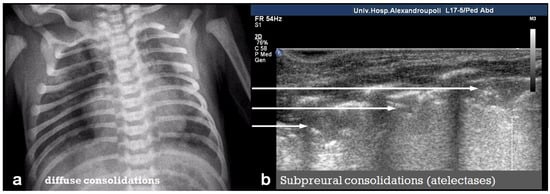

MAS is a serious respiratory condition that occurs when a newborn infant inhales meconium-stained amniotic fluid, leading to airway obstruction, chemical pneumonitis, and impaired gas exchange. LUS in MAS typically reveals diffuse lung consolidations, often bilateral and patchy, reflecting widespread alveolar involvement due to inflammation, atelectasis, or surfactant inactivation (Figure 17).

Meconium aspiration syndrome: (a) CXR with small diffuse consolidations, (b) LUS reveals coalescent B-lines and small subpleural lung consolidations (arrows).

These consolidations may appear as subpleural hypoechoic areas with hepatization and air bronchograms [37]. In addition, both focal and confluent B-lines may be observed, indicating interstitial fluid accumulation secondary to inflammation or pulmonary edema. Pleural irregularities, including thickening and disruption of the pleural line, are also common and suggest subpleural injury or inflammation. The combination of these findings in conjunction with a perinatal clinical history can help to differentiate MAS from other neonatal respiratory disorders such as Transient Tachypnoea of the Newborn (TTN) or Respiratory Distress Syndrome (RDS) and supports the use of LUS as a valuable bedside diagnostic tool in the neonatal intensive care setting [8,16,17,29,49,50].